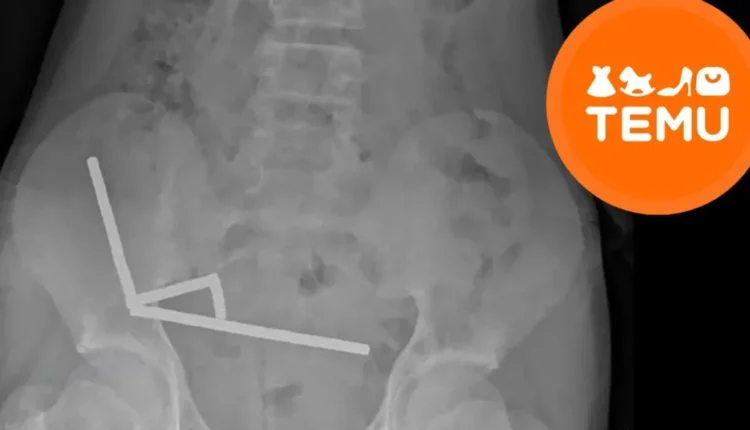

जेव्हा डॉक्टरांनी एक्स-रे काढला तेव्हा त्यांना काहीतरी भयानक दिसले. त्याच्या आतड्यांमध्ये चार लांब रेषांमध्ये चुंबक एकत्र जमले होते. त्यांच्यातील शक्तीने त्याच्या आतड्यांचे काही भाग एकत्र खेचले, रक्त प्रवाह बंद झाला आणि अनेक ठिकाणी ऊती नष्ट झाल्या. यामुळे डॉक्टरांनी “नेक्रोसिस” म्हटले, म्हणजे त्याच्या आतड्याचे काही भाग मरण्यास सुरुवात झाली.